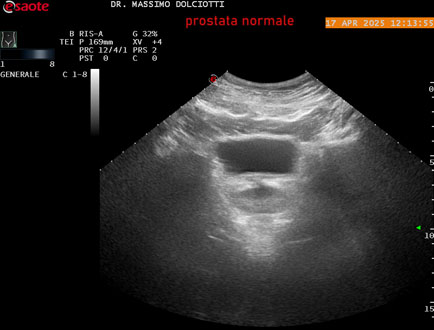

Strumento: Esaote MyLab Eight

Sonda: Convex Multifrequenza 1-8 MHz, Endocavitaria Multifrequenza 3-9 MHz e 3-13 MHz

Età Paziente: M 35 anni

Motivazione dell'esame: disuria.

Commento all'esame: le immagini ed il video documentano la prostata di ecostruttura regolare e morfovolumetria normale con diametro trasversale di 40 mm, diametro anteroposteriore di 21 mm e diametro longitudinale di 43 mm, con volume prostatico calcolato di 18 cc (v.n. < 20 cc), il profilo prostatico è regolare e netto, non si documentano calcificazioni intraghiandolari, la vascolarizzazione della ghiandola è normale. La vescicola seminale destra presenta diametro longitudinale di 44,4 x 7,8 mm, la vescicale seminale sinistra ha diametro longitudinale di 45,3 mm x 7,2 mm.

Conclusioni: prostata normale (normal prostate).